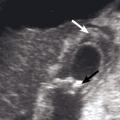

L’échographie abdominale a l’inconvénient d’être opérateur-­dépendante. Ses principales indications sont la lithiase biliaire et ses complications, des douleurs abdominales chez les patients minces et surtout chez la femme pour rechercher une pathologie gynécologique en utilisant le cas échéant des sondes endocavitaires. Ainsi, l’échographie est utile pour affirmer la lithiase biliaire et la cholécystite aiguë (fig. 1) ou objectiver une dilatation de la voie biliaire principale (VBP), rechercher une urétéro-hydronéphrose et des signes indirects en cas de colique néphrétique (fig. 2 et 3), débrouiller le diagnostic des douleurs abdomino-­pelviennes chez la femme.

L’échographie peut montrer une discrète asymétrie des cavités excrétrices rénales, voire l’obstacle lithiasique avec dilatation d’amont (fig. 2 et 3). L’uroscanner complète le bilan et localise si besoin le calcul. Outre le traitement de la cause (calcul, compression extrinsèque…), le traitement antalgique est primordial : anti-inflammatoires non stéroïdiens (AINS), paracétamol, anti­spasmodiques voire dérivés morphiniques. On procédera à la pose d’une sonde urétérale en cas d’anurie (rein unique), de fièvre sur rétention du haut appareil ou de crise hyperalgique.